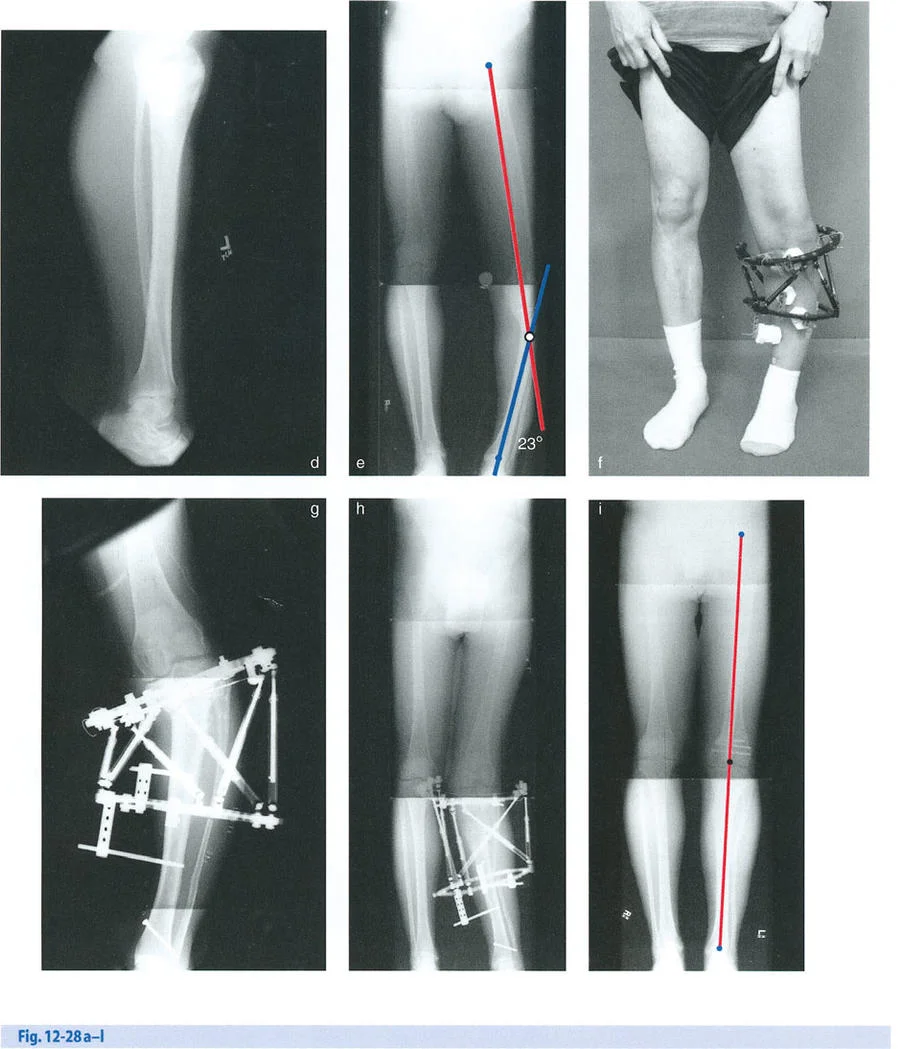

- الأشعة السينية الأمامية الخلفية والجانبية (AP and Lateral Radiographs): تُستخدم لتقييم التشوه في المستويين التاجي (التقوس للداخل أو الخارج) والسهمي (التقوس للأمام أو الخلف).

- التصوير المقطعي المحوسب (CT Scan): يُعد حاسمًا لتقييم التشوهات الدورانية (الالتواء) التي لا تظهر بوضوح في الأشعة السينية التقليدية، ولإجراء قياسات ثلاثية الأبعاد دقيقة للعظم.

- بعد الحصول على صور الأشعة السينية والتصوير المقطعي، يقوم الأستاذ الدكتور محمد هطيف بإدخال هذه البيانات في برامج تصميم متخصصة بمساعدة الحاسوب (CAD).

- تسمح هذه البرمجيات بتحليل دقيق للتشوه في جميع درجات الحرية الست (الانحناء في مستويين، الإزاحة في مستويين، الطول، والدوران).

- يمكن للدكتور هطيف "محاكاة" الجراحة افتراضيًا، وتحديد مكان القطع العظمي (Osteotomy) بدقة، وتخطيط التصحيح النهائي قبل حتى البدء في الإجراء الجراحي. هذا التخطيط الافتراضي يسمى "تخطيط الدمية الورقية" (Paper Doll Planning).

إطار تايلور المكاني وبرمجيات التصميم بمساعدة الحاسوب CAD

لقد أحدث إطار تايلور المكاني (TSF) ثورة في تطبيق مبادئ بالي. يعتمد هذا الإطار على منصة ستيوارت-غوف (Stewart-Gough platform)، وهي آلية روبوتية سداسية الأرجل تُستخدم في محاكيات الطيران. يتكون إطار تايلور المكاني من حلقتين متصلتين بستة دعامات تلسكوبية. يتيح تعديل أطوال هذه الدعامات الستة تصحيحًا متزامنًا لجميع درجات الحرية الست.

يُعد برنامج التصميم بمساعدة الحاسوب (CAD)، الذي طورته شركة Orthocrat Ltd. في الأصل، أداة لا غنى عنها للتحليل التفصيلي والدقيق للتشوه ومعلمات التركيب باستخدام الصور الإشعاعية الرقمية. يتطلب هذا البرنامج من الجراح إدخال ثلاث مجموعات متميزة من البيانات:

- معلمات التشوه: حجم التشوه بستة محاور (على سبيل المثال، 10 درجات تقوس للداخل، 5 درجات تقوس أمامي، 15 ملم تقصير، إلخ).

- معلمات الإطار: حجم الحلقات والأطوال الأولية للدعامات الست.

- معلمات التركيب: كيفية وضع الحلقة المرجعية في الفضاء بالنسبة لقطعة العظم المرجعية (الإزاحات الأمامية الخلفية، الجانبية، والمحورية).